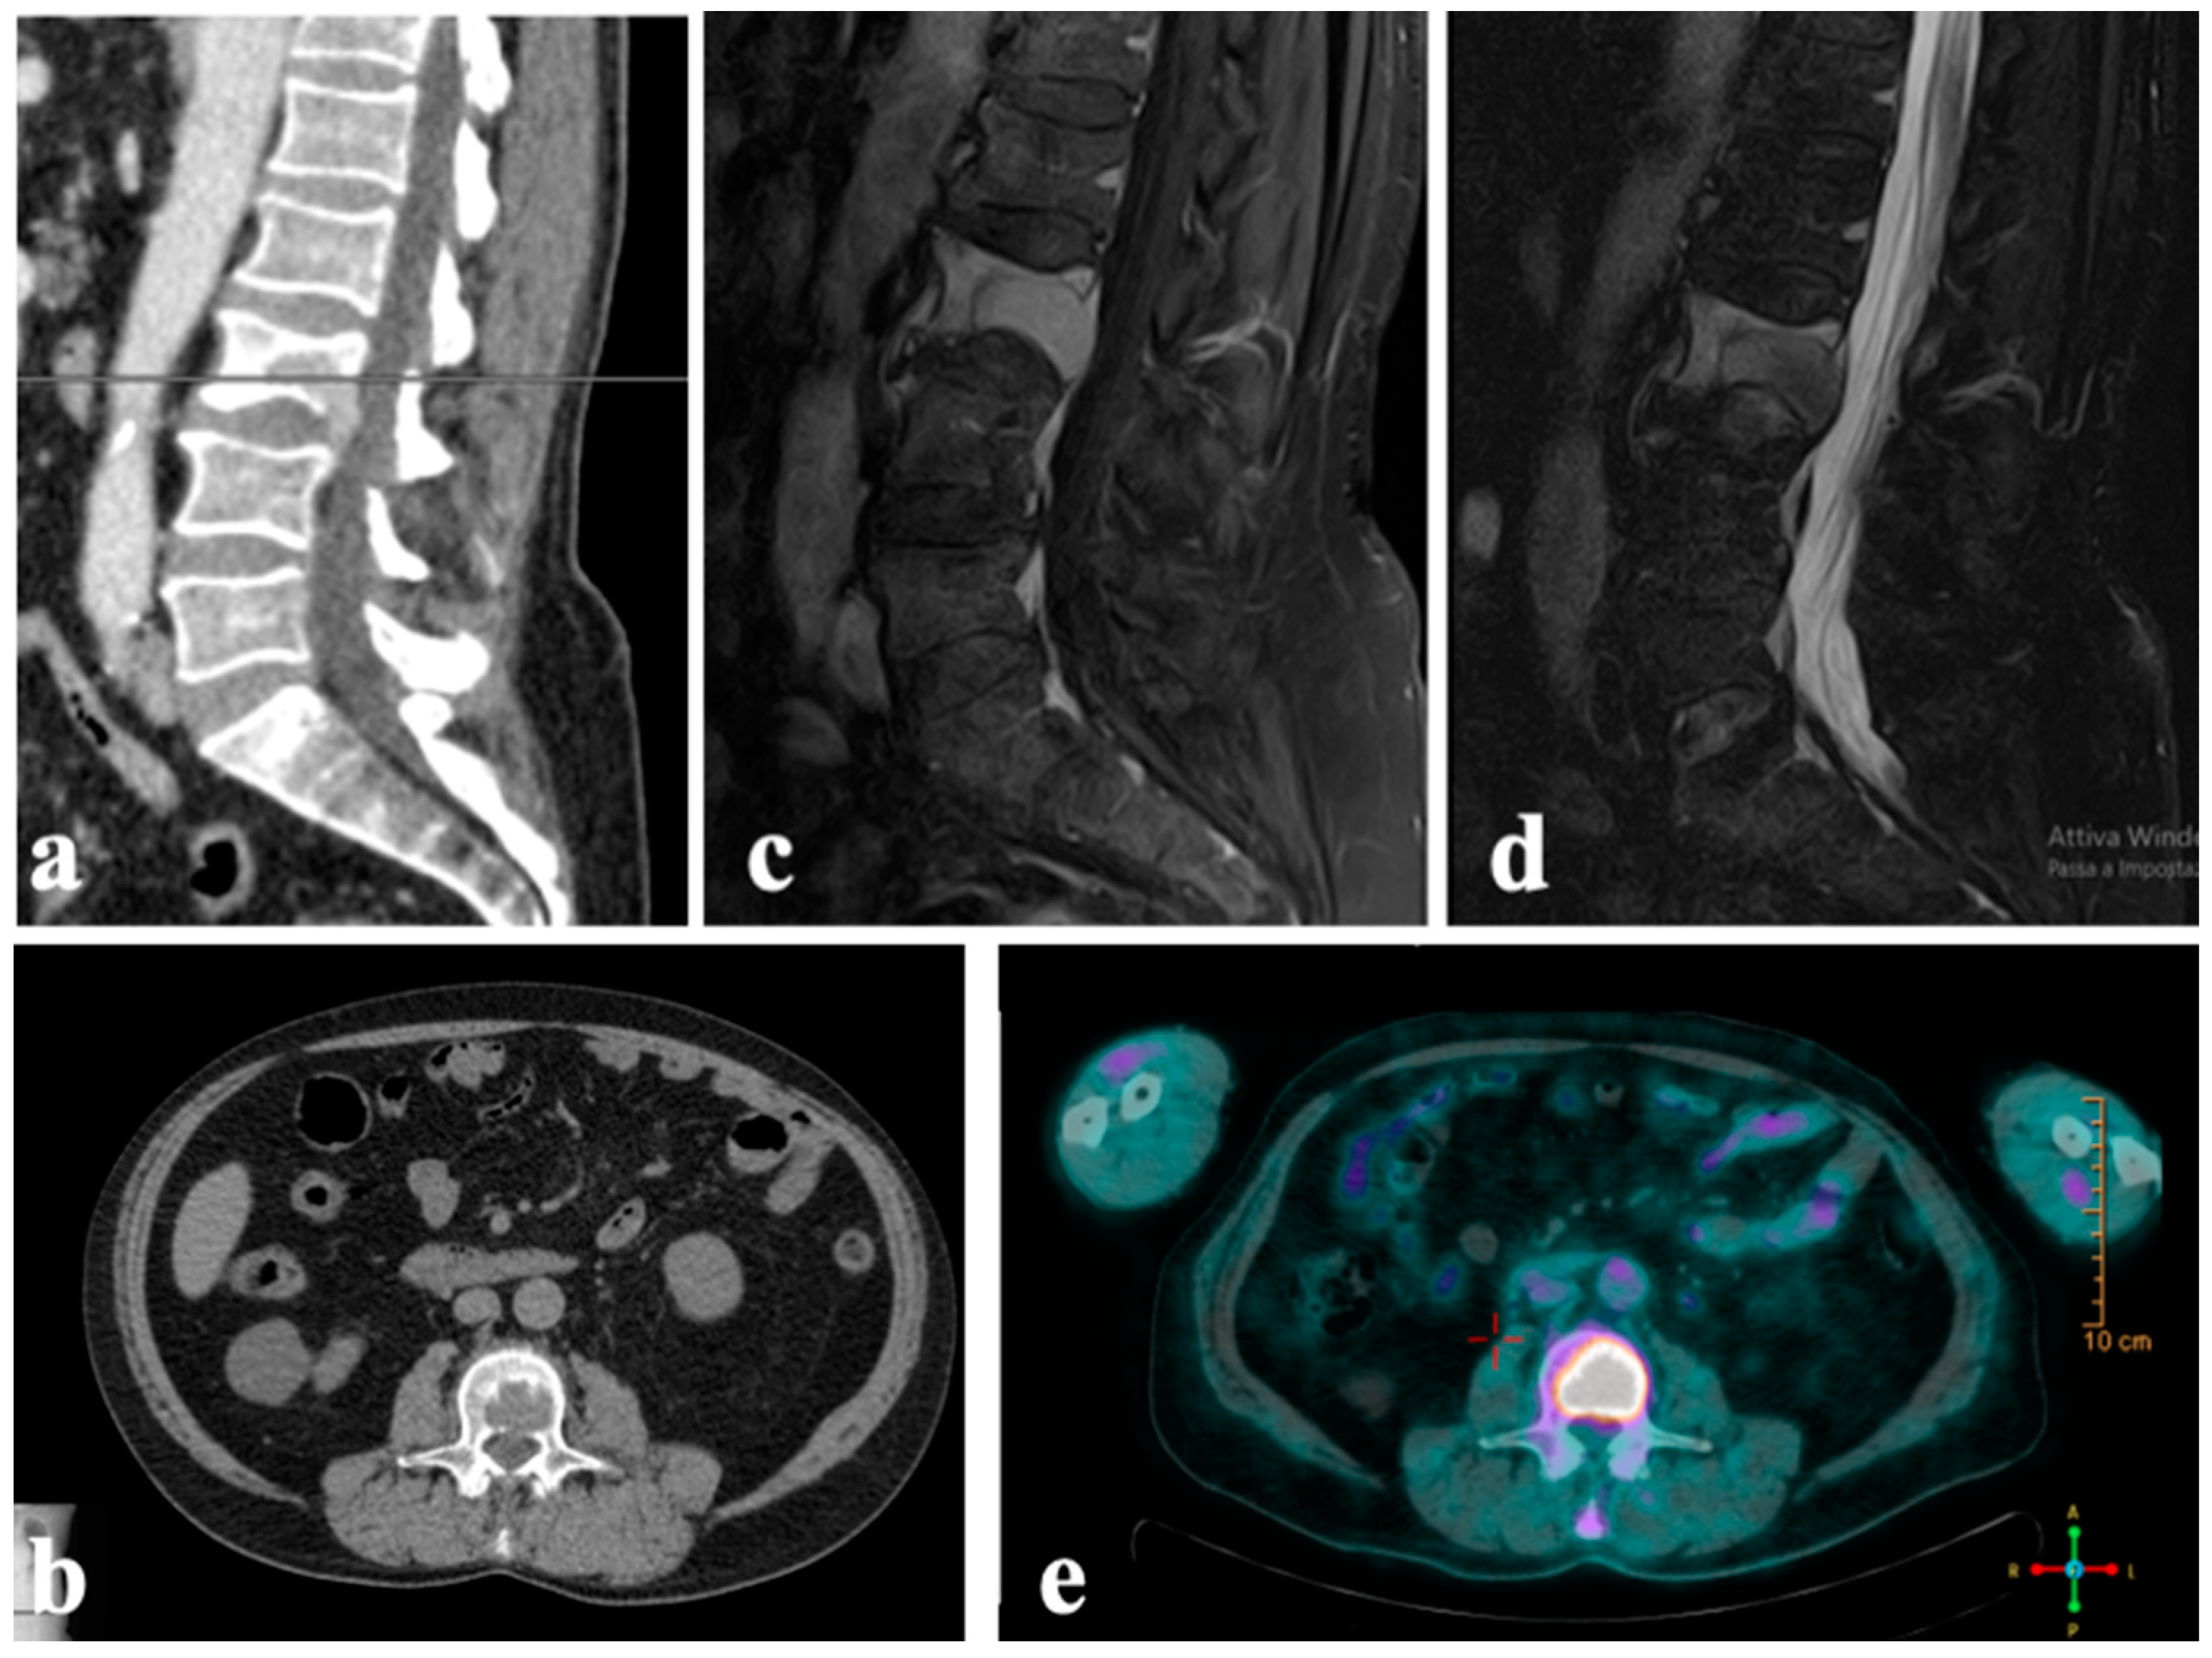

| [12] (2015) | Case report | 1 | Melanoma | Lumbar | Surgical procedure: Hemilaminectomy | Pain relief Good MRI response |

| [16] (2018) | Case reports | 2 | N/A | Lumbar Thoracic | Minimally invasive: Transpedicular Approach | N/A |

| [17] (2019) | Case reports | 2 | Breast carcinoma; Lung carcinoma | Lumbar | Percutaneous CT guided (pedicles\vertebral body) | Pain relief Good MRI response |

| [18] (2023) | Case series | 40 | Thyroid carcinoma; Lung carcinoma; Sarcoma; Others (*) | Cervical Lumbar Thoracic | Percutaneous CT guided (pedicles\vertebral body) | Pain relief Neurological improvement Good MRI response |

| Present study | Case series | 3 | Myxofibrosarcoma; Squamous cell carcinoma of skin; leiomyosarcoma | Lumbar | Transpedicular approach during surgical procedure | Pain relief and neurological improvement ** |